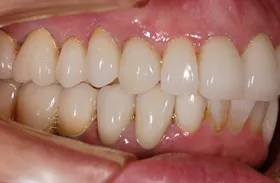

矯正及びインプラントで治療のケース

■治療前1

■治療後1

■治療前2

■治療後2

■治療前3

矯正により歯の位置を適正な位置に動かし、歯の無い部分に対してインプラントにより回復したケースです。

■治療後3

上下とも美しい歯並びと噛み合わせになりました。 形だけでなく、色みも自然な仕上がりです。

| 主訴 | 下の歯が1本無いので歯ならびが良くなく、かみ合わせも悪い |

| 治療方法 | 矯正治療+インプラント治療+補綴治療 |

| 治療期間 | 約3年 |

| 通院回数等 | 約35回 |

| 費用 | 約160万円 |

| リスク・副作用 | 矯正治療も行ったので治療期間が長くなった インプラント術後の腫れ・痛み |